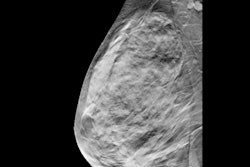

Ultrasound alone "adequately" evaluated 93.7% of recalled masses (178/190). Of the 93 lesions that underwent needle biopsy, 38 were found to be invasive cancers. Ultrasound alone evaluated 35 of these cancers, while the remaining three were evaluated with ultrasound and diagnostic mammography. Ultrasound alone had a sensitivity of 94.9% for cancer diagnosis.

At median follow-up of 25 months, six cancers were identified in patients with initially benign workup. Three of these were with ultrasound alone while the other three were with ultrasound plus diagnostic mammography. Ultrasound alone had two false-negative cancers.

"Omitting diagnostic mammography when ultrasound is negative has a low false-negative rate," the study authors wrote.